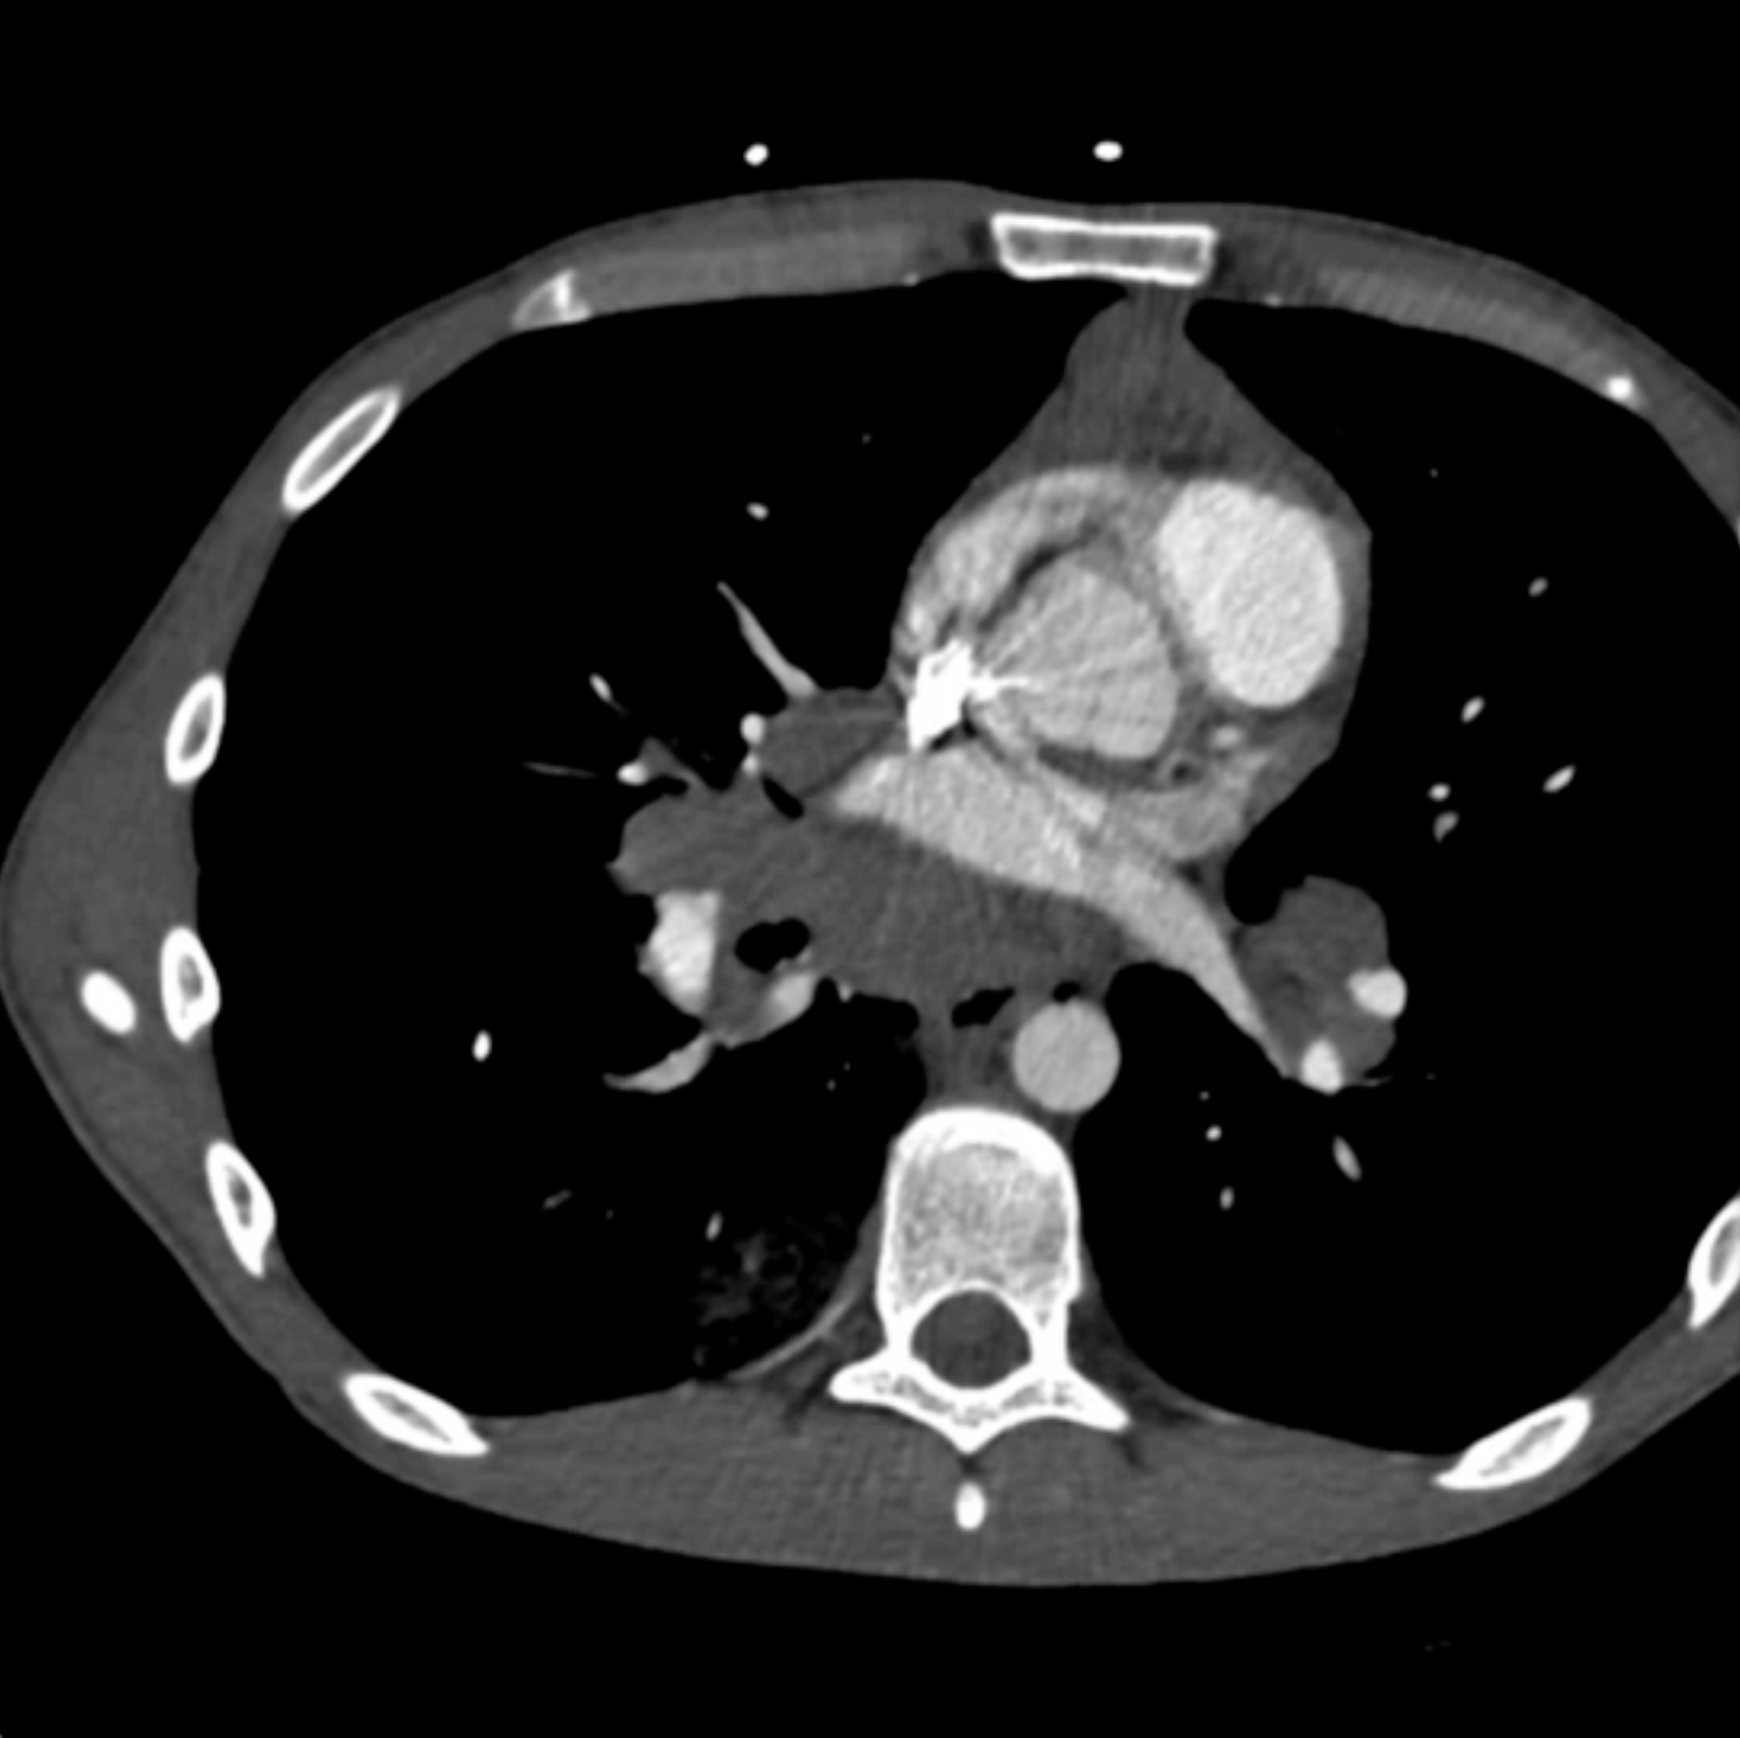

Large Cell Lymphoma